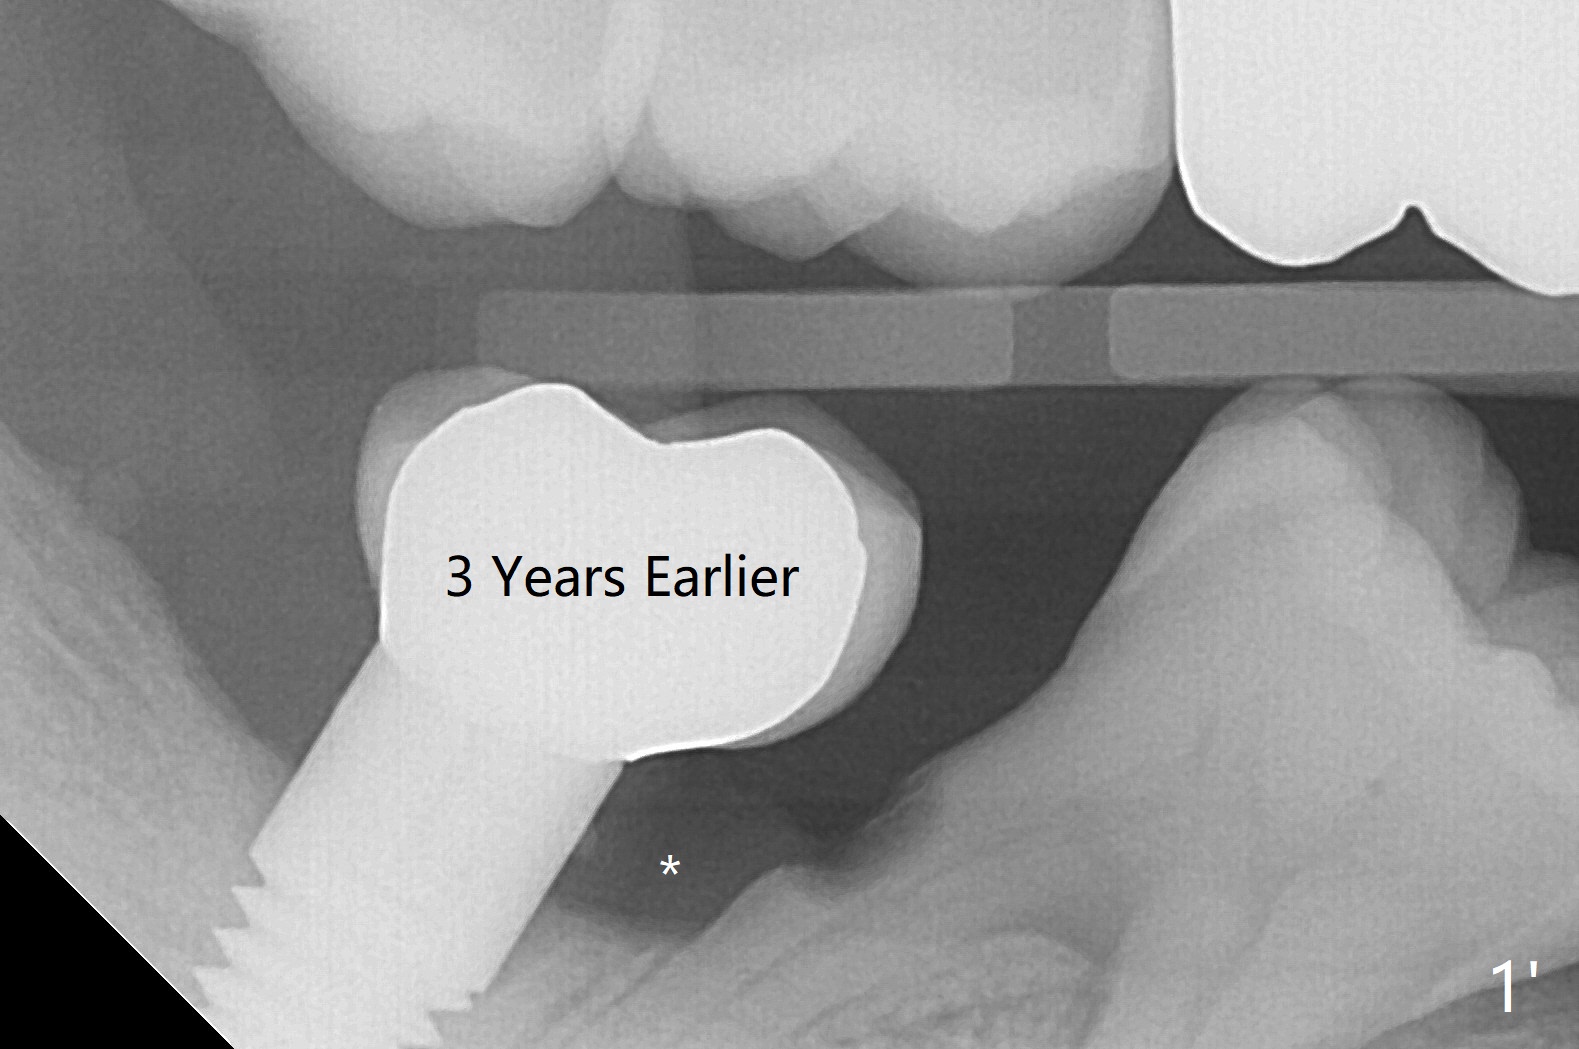

邻近植牙龈下植骨(比较图一'(*),图一(<))。